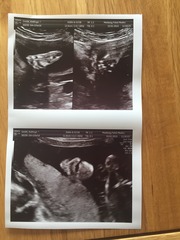

Afternnon ladies

Congrats Chook! Lovely pics :)

Lovely face shot of your baby chook.